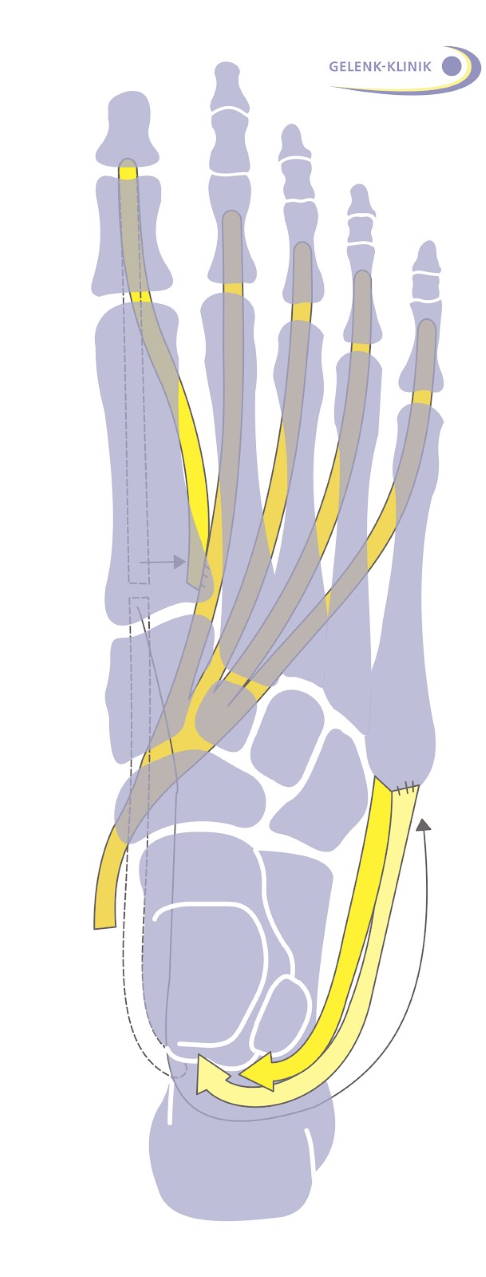

In der frühen Krankheitsphase ist der außen am Fuß ansetzende Musculus peroneus brevis, also der kurze Wadenbeinmuskel, betroffen. Dieser Muskel ist ein Antagonist (Gegenspieler) des hinteren Schienbeinmuskels. So resultiert aus der Schwäche des außen ansetzenden Muskels eine Fehlstellung mit vermehrtem Zug des Fußes nach innen. Diese Stellungsanpassung erfolgt im Gelenk vor dem oberen Sprunggelenk, also im Chopart-Gelenk. Der Fuß stellt sich hier von oben gesehen mehr nach innen ein (Supinationsstellung).

Bei dieser Schwächung kommt es auch zu einem Ungleichgewicht zwischen den beiden Wadenbeinmuskeln M. peroneus longus und brevis. Daher überwiegt bei der Schwächung des außen ansetzenden kurzen Wadenbeinmuskels (M. peroneus brevis) die Kraft des langen Wadenbeinmuskels (M. peroneus longus), der von außen unter dem Fuß hindurch unten, innen am Mittelfuß ansetzt. Dieses Ungleichgewicht führt zu einer vermehrten Senkung des ersten Mittelfußknochens. Der Fußaußenrand wird durch die mangelnde Muskelführung nicht mehr geführt und verliert die Kontrolle (Steilstellung des 1. Strahles).

Mögliche komplette und halbe Sehnentransfers

Die Sehnentransfers werden nach ihrem verwendeten Muskel und der zu verstärkenden Muskulatur bezeichnet. Ein Transfer des M. flexor digitorum longus auf Peroneus brevis ist eine Versetzung einer der Beugemuskeln der Kleinzehen von innen auf den geschwächten kurzen Wadenbeinmuskel nach außen. Die Wirkung verbessert eine geschwächte Steuerung des Fußaußenrandes.